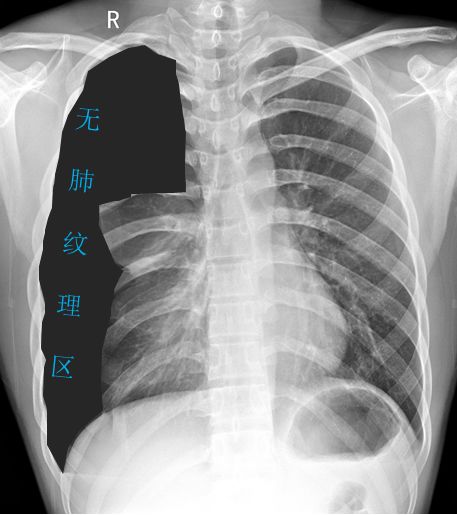

病例2

病例2患者的X线胸片

黑色区域:无肺纹理区域。肺叶压缩约70%;

蓝色虚线:被压缩肺组织边缘;

紫色箭头:肋膈角可见液-气平面;

橙色实线:第3、4肋骨前端骨桥关节,肋骨骨桥(先天变异);

可见心影及纵隔向对侧轻度移位。